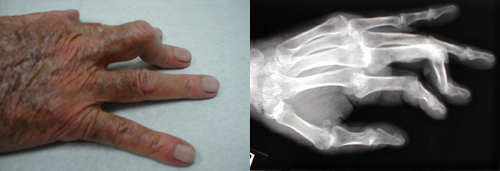

تشوه Boutonniere في الإصبع الوسطى

يترافق مع التهاب المفاصل الريثاني المزمن .